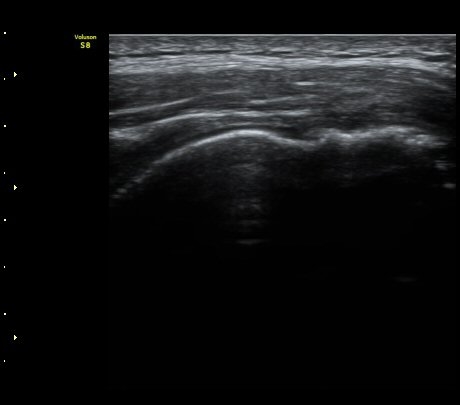

±Ø»ó°ÇȾ´Ü¸é°Ë»ç¿¡¼­ ±Ø»ó°ÇÀÇ ±¤¹üÀ§ÆÄ¿­ ¼Ò°ßÀ» º¸ÀÓ(»çÁø 4)